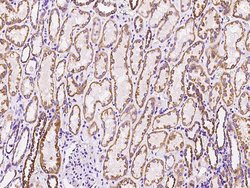

MRPL12 Polyclonal Antibody for Western Blot, ICC/IF, IHC (P), IP

| Immunohistochemistry (Paraffin), Immunoprecipitation, Western Blot, Immunocytochemistry | |